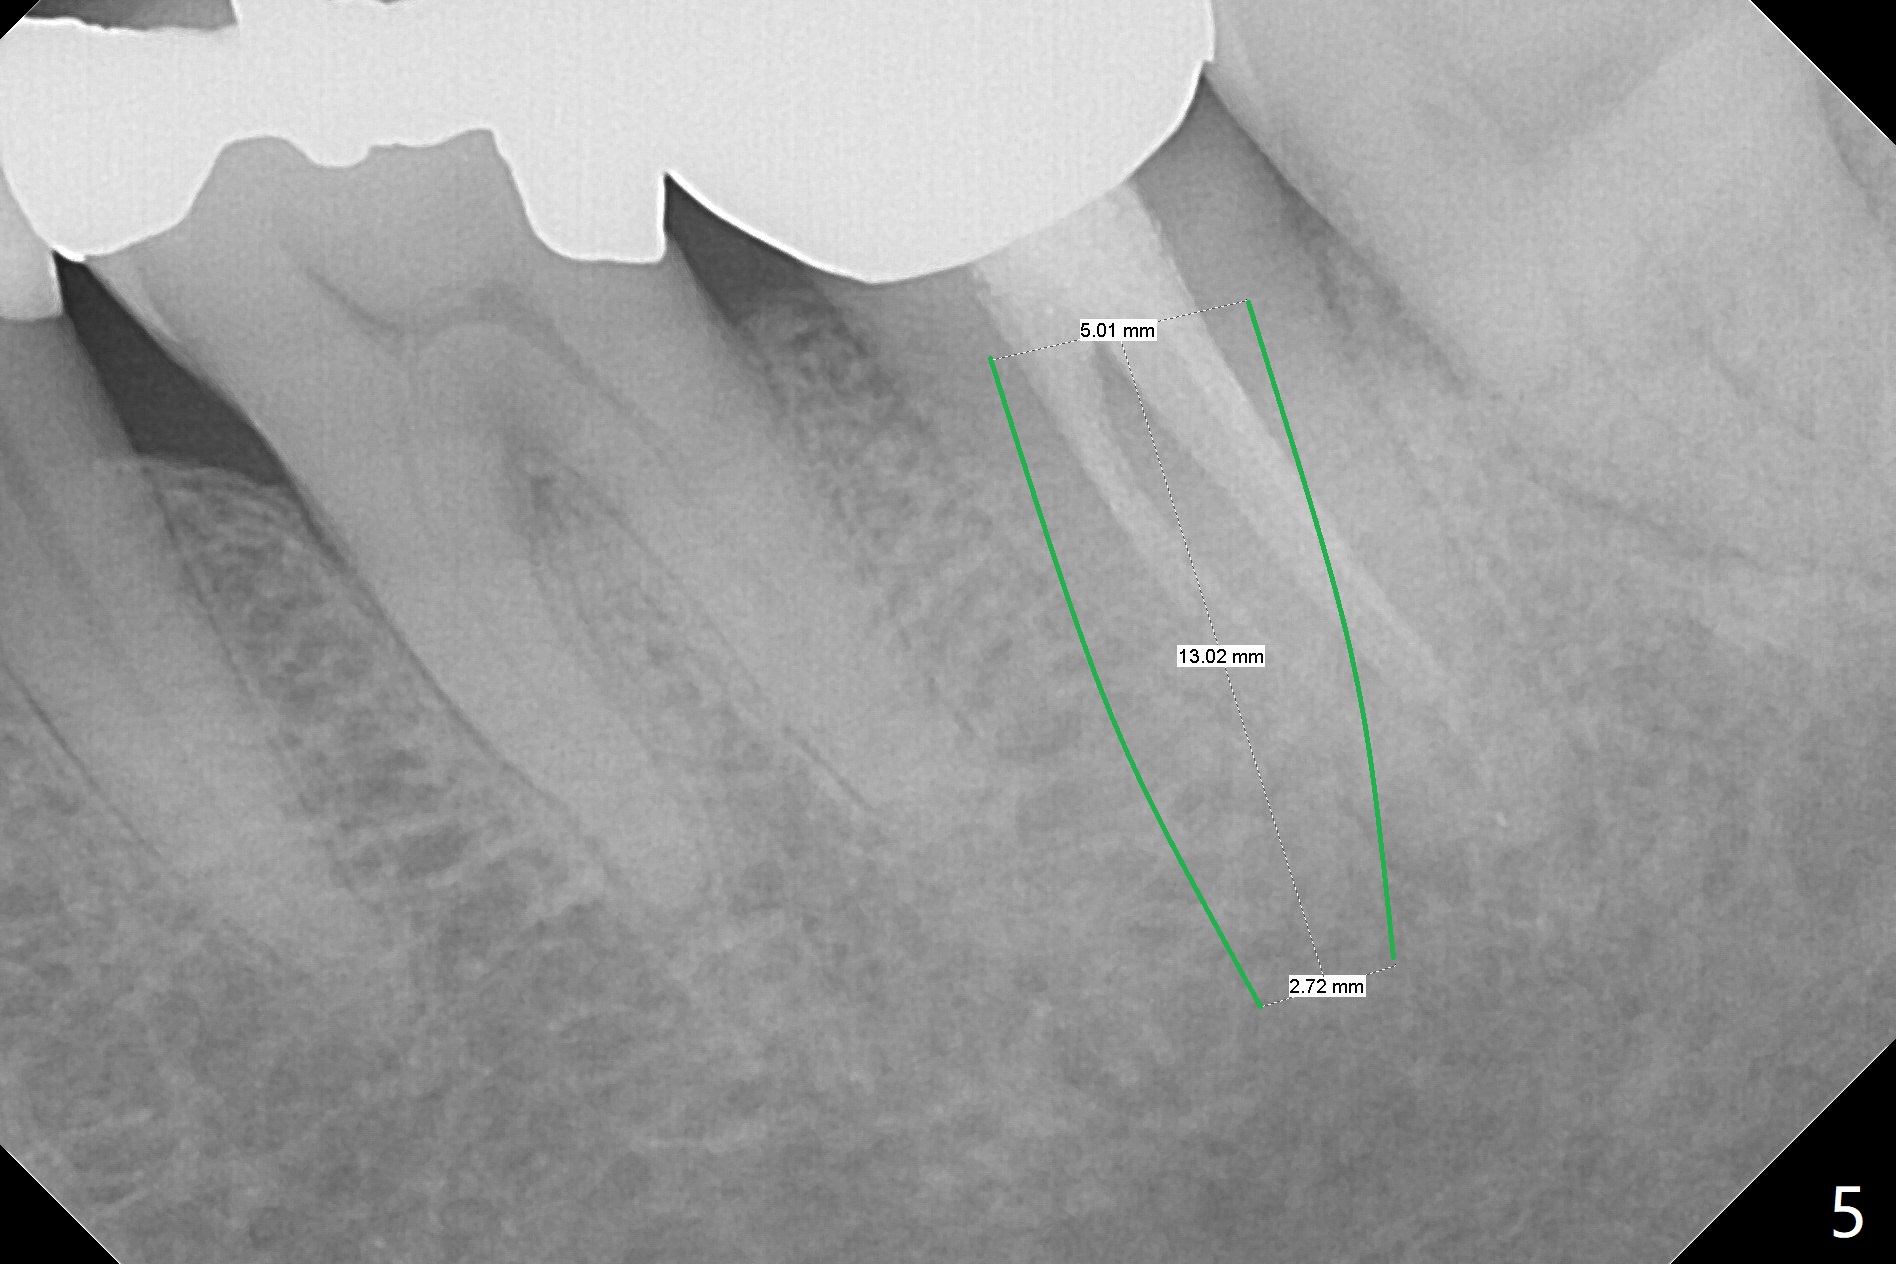

In all, the patient should be a heavy bruxer. When extraction and immediate implant is done at #18, immediate provisional should be low and stable (keep bone graft in place). It appears that a temporary abutment can accomplish the purpose. An IS one has been trimmed. There are 2 options for implant placement: along the long axis of the socket (Fig.4 using taps for osteotomy) and in the mesial slope of the socket (Fig.5 using drills). If the bone level implant (tap) does not work, switch to tissue level one (Fig.6).